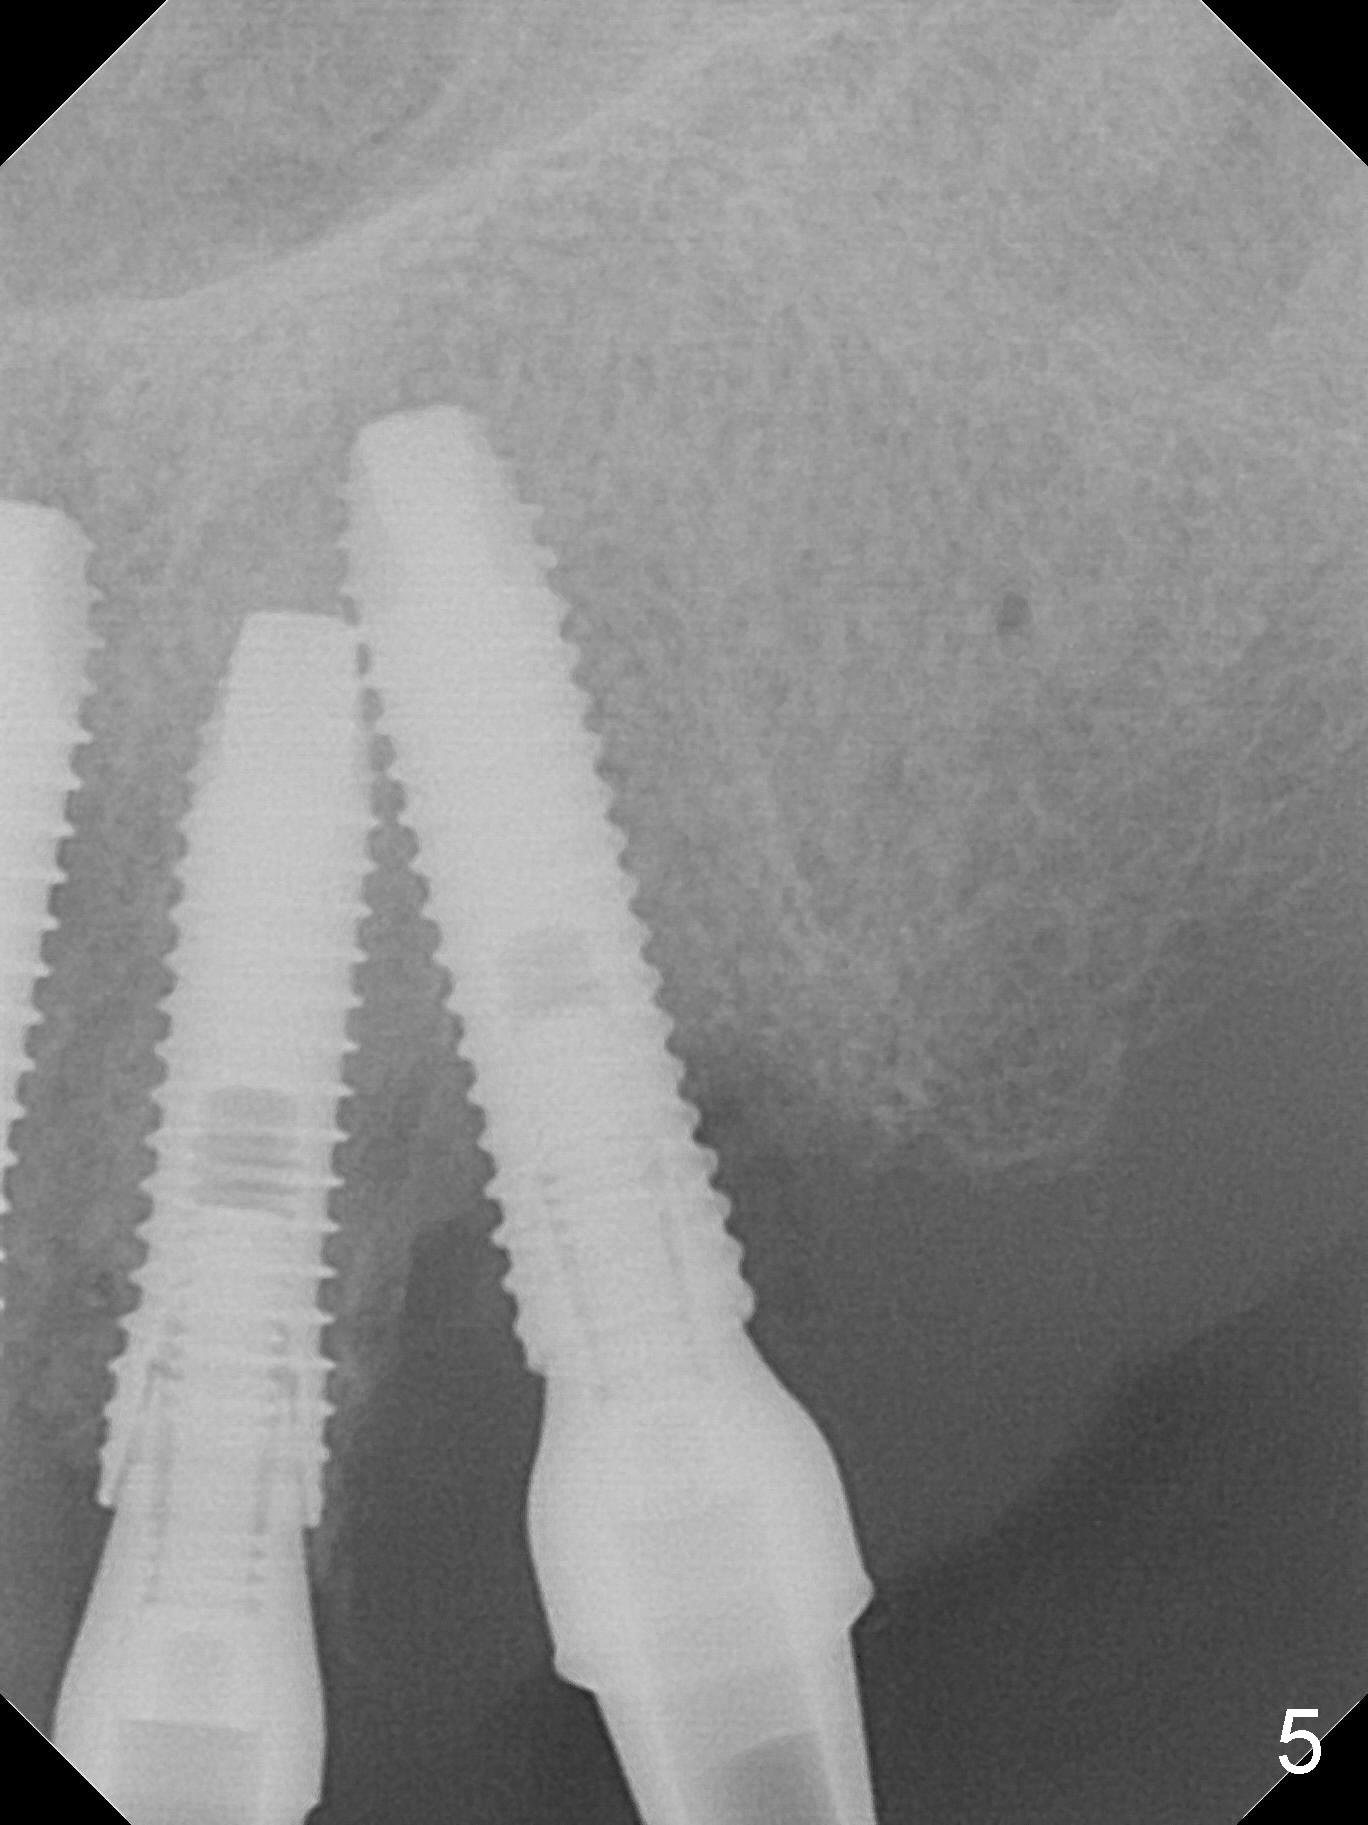

The dentition is poor except #6 and 8 (Fig.1). The gingiva is erythematous at #9-11 (Fig.2). The teeth #9 and 10 are extracted first; a 4x16 mm UF implant is placed at #9, while a 2 mm pilot drill is at the site of #10 (Fig.3). The implant at #9 is placed deeper with placement of 4.5x5.5(5) mm abutment; a 3.8x15 mm implant is placed at #10 initially (Fig.4). While the latter is placed deeper, a 4x16 mm implant is placed at #11 (Fig.5 after removal of #11-15 FPD (fixed partial denture)). In fact the trajectory at #11 is not difficult to be changed with 2 mm drill (Fig.6). After use of 3 mm drill, the implant is reinserted at #11 with ideal trajectory (Fig.7). After further seating of the implant at #11, graft is placed in the remaining sockets of #9-11 (Fig.8 *; later more graft is placed mesial to #11 implant (^)). Finally, a 4.5x7(5), 4.5x15° B (4) and 5.5x7(5) mm abutments are tightened and prepared (Fig.9) for splinted provisional at #9-10.

There is 1-2 thread exposure mesial and distal at #10 two years postop (Fig.20'), which may be related to the small fistula labially (Fig.20 >). It appears that the implant at #10 was placed too high (Fig.21) and labially (Fig.22). In fact the bridge fractures between #12 and 13 during pandemic.